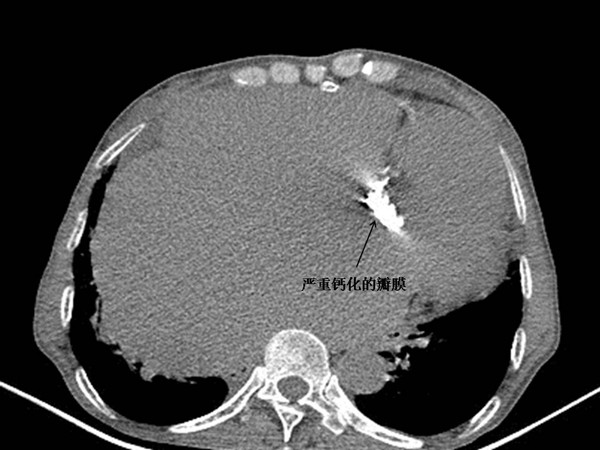

患者心脏病情极为严重,严重钙化病变导致二尖瓣及主动脉瓣重度狭窄,心功能极差,心脏极度扩大,临近终末期状态,行常规瓣膜手术修复风险极大。手术需要同时处理三个瓣膜(二尖瓣及主动脉瓣置换、三尖瓣上环成形)及左心房(左心房折叠成形及左心耳缝闭),步骤繁杂,心脏停跳时间长,体外循环及手术打击对于患者脆弱的心脏来说可能是压死骆驼的最后一根稻草,手术结束后可能无法停机脱离体外循环最终死亡。加之患者合并有重度呼吸功能不全、肾损害、血小板减少及白细胞减少等情况,即使心脏挺过手术打击这一关,围术期仍可能出现以下情况导致病情恶化、功亏一篑:血小板减少及体外循环打击导致凝血紊乱术后大出血;肺功能极差,术后无法脱开呼吸机导致呼吸衰竭、严重肺部感染;脆弱的肾脏在手术及体外循环打击下术后可能出现肾功能衰竭;术后ICU住院时间长,患者白细胞数低,营养不良,可能出现严重院内感染等并发症。

经过术前精心准备,手术一刻终于来临,手术及麻醉团队严阵以待。麻醉科吕建瑞主任、李芳及李有才教授等众多麻醉医师的通力协作,在上半身抬高50度的艰难体位下为患者麻醉插管,期间血压下降,使用大剂量升压药物艰难维持血压。裴斐主任及万俊哲、张伟主治医师组成的手术团队迅速完成消毒、铺巾,打开患者胸腔后发现心脏极度扩张膨大且转位,视野中仅可见右心房及上腔静脉,心脏搏动无力、几近停搏。手术团队在极短时间内建立起体外循环辅助,心脏终于趋于平稳。打开心脏发现瓣膜严重钙化、坚硬如骨。手术按计划有条不紊进行,切除病变二尖瓣及主动脉瓣膜,置换为人工机械瓣膜,扩大的三尖瓣上环成形,左心耳缝闭,巨大左房予以折叠缩小。术中从患者仅40公斤的瘦弱躯体中体外循环竟超滤出多达8100ml液体。术后患者心脏顺利复跳停机,心脏仿佛卸除了重担,搏动有力,焕发出新机。当患者推出手术室的一刻患者家属相拥而泣,而此时手术团队仅仅是松了一口气,心头的重担还无法卸下来,患者还将面临术后心肺功能恢复、出血、感染、肾功衰等一道道难关!患者在监护室很快出现严重心律紊乱、频发短阵室速,血压偏低,胸腔引流持续偏多,手术切口广泛渗血,持续40℃高热….裴斐主任带领手术团队同重症医学科王小闯主任、韩俊丽主治医师等不辞辛劳昼夜守护在患者床旁,十余道输液泵将各种血管活性药物徐徐泵入,血小板、新鲜血浆等不断输入患者身体。患者病情逐渐稳定,终于度过术后危险期,术后第四天脱开呼吸机并拔除气管插管,术后第五天转回普通病房,恢复良好,现已顺利出院,喜获新生。